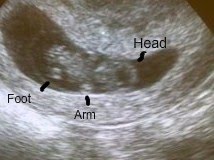

The first proof that we're adding to the family

Baby's First Photograph. I pointed out the important features so you can figure it out!

See him waving at us?

See the penis on the left? That's our Rex